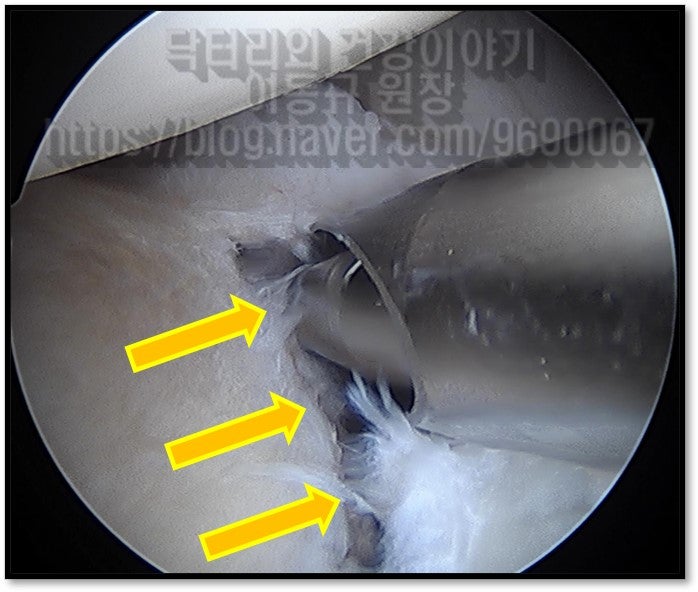

종합적으로 판단했을때 이학적 검사상 전방불안정성이 보이며 MRI 상 전방 관절와순 파열이 관찰되었습니다. 진단은 어깨 탈구로 인한 전방 관절와순 파열 이며 이에 대해 수술적 치료를 하였습니다.

이 환자분에게 무엇이 잘못되었을까요? 우선 이학적 검사만 제대로 했어도 어떠한 질환이나 손상이 의심되는지 체크할 수 있었습니다. 둘째 MRI 검사한 것을 자세히 살펴만 봤어도 병변을 놓치지는 않았을 겁니다. (단순히 판독지만 보고 MRI 를 보지않는 경우도......) 전방관절와순 파열로 인한 불안정성이 있는 환자를 도수치료만 하다니... 그러니 증상이 악화될 수 밖에 없지요... 모든 어떠한 질환이든 정확한 진단이 이루어져야 정확하고 제대로된 치료를 할 수 있습니다. 치료를 하고 있음에도 증상이 악화되거나 호전되지 않을때 한번쯤은 진단이 제대로 된 것인지 생각해볼 필요가 있겠습니다.